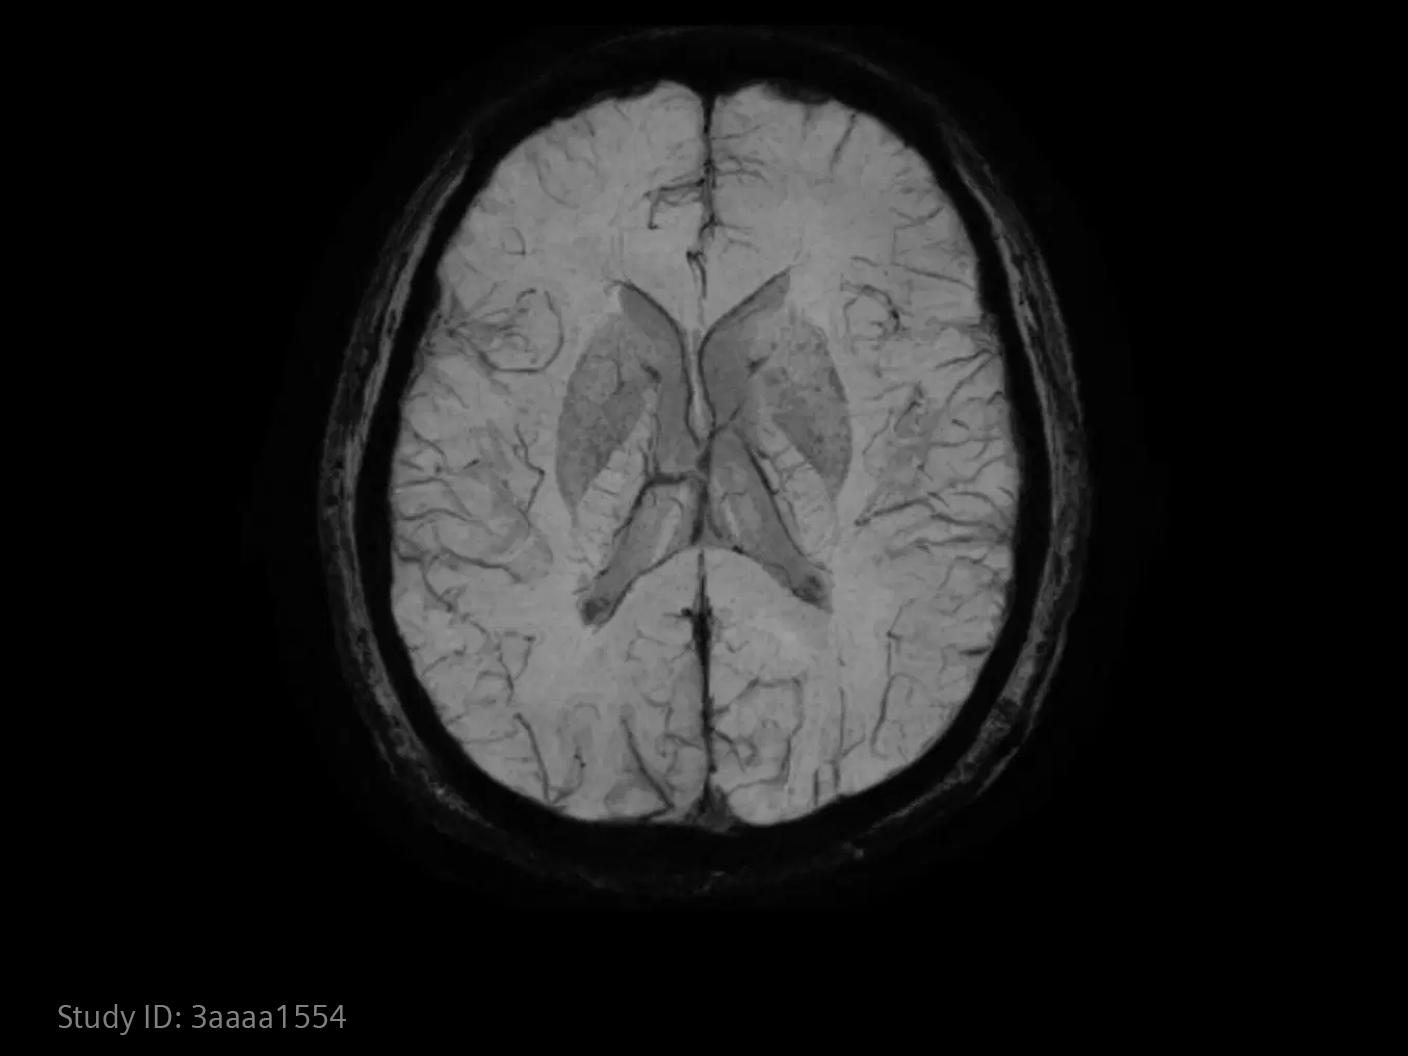

How advanced imaging and AI transform stroke workflow

In stroke care, time is brain. Rapid and accurate imaging is crucial to assess the extent of brain injury and guide immediate treatment. Angiography, MRI, CT, ultrasound, and lab diagnostics are essential tools in identifying stroke type, location, and severity. Advances in imaging technology now allow for even faster acquisition, improved resolution, and enhanced visualization of brain tissue and blood vessels. Innovations such as perfusion imaging, real-time vascular mapping, and AI-assisted diagnostics are transforming stroke workflows and enabling precise, timely interventions.